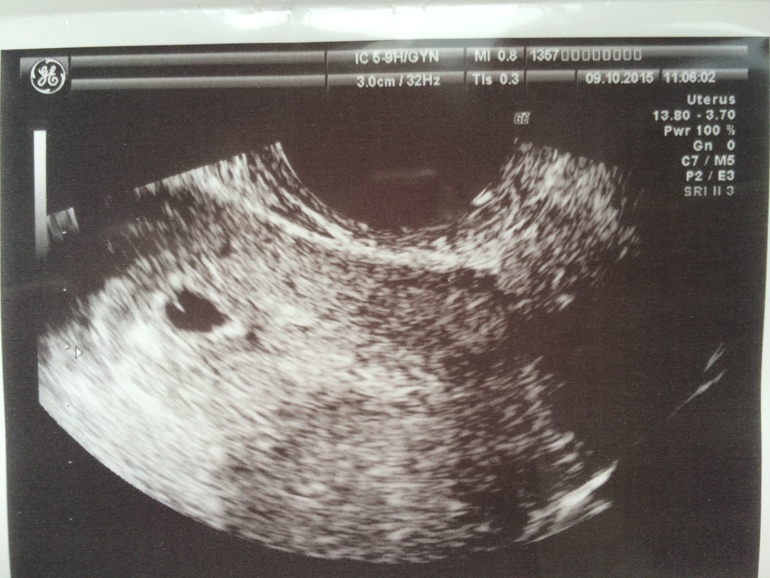

мое счастье,мое кунжутное зернышко-я так тебя люблю))

ХГЧ 11ДПО - 23,13 ДПО - 95, 21 ДПО - 2682

Мой малыш в матке,Боже,как же я счастлива. Моя единственная труба меня не подкачала и доставила мою лялю, туда,куда должно.

Девочки,смущает только, что плодное яйцо овальное,должно же быть куглое???переживаю теперь из-за этого. Я параноик,да счастливый,но параноик)))))